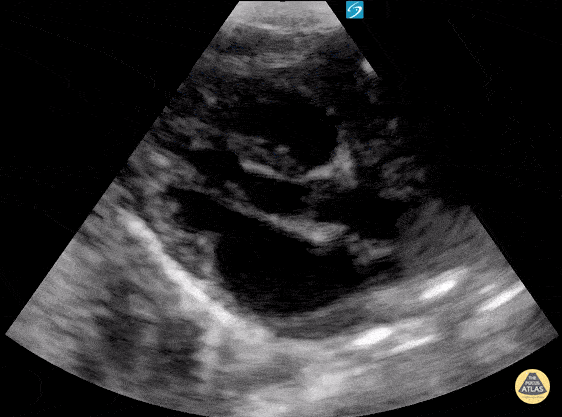

Newborn with SVT. Contributor: Paul Khalil, MD Nicklaus Children's Hospital @khalil3paul